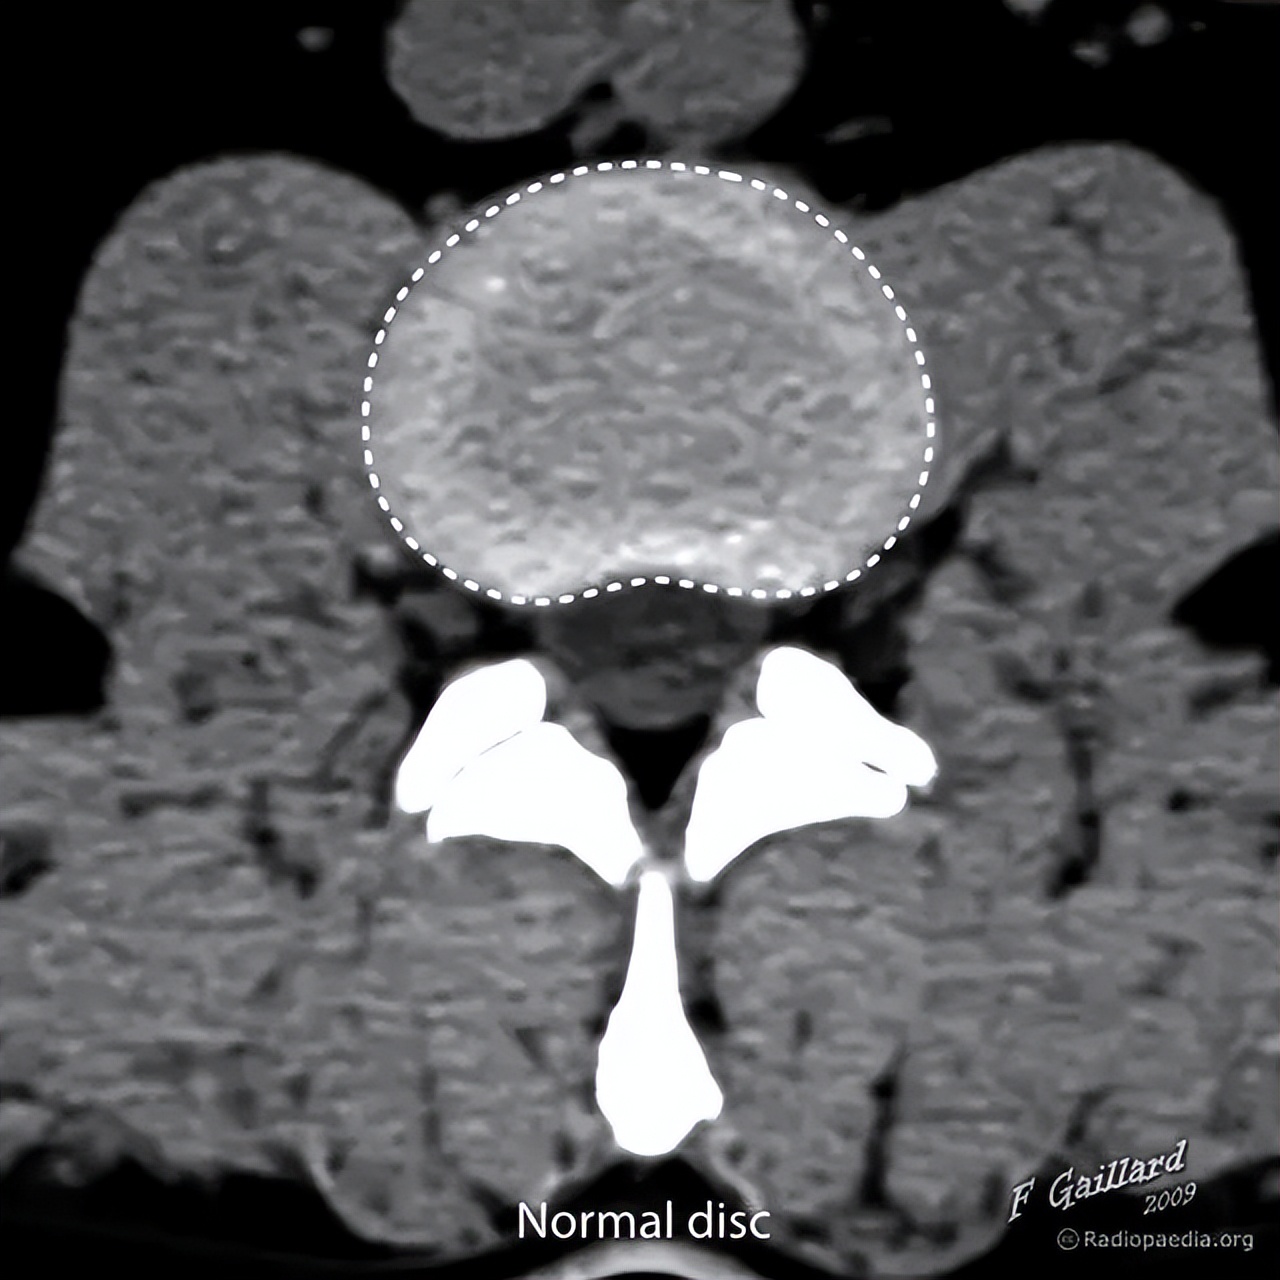

正常的椎间盘示意图,椎间盘由周围的纤维环和中心的髓核组成

1为纤维环,2为髓核

此为影像学图像,正常椎间盘(浅灰色区域)的周围不超出椎体边缘